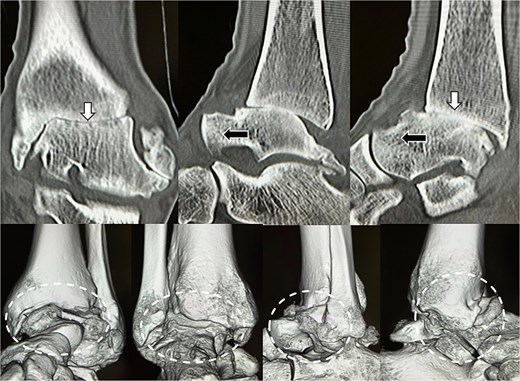

Preoperative radiographs and computed tomography (CT) demonstrated complete loss of the tibiotalar joint space, talar subluxation, and extensive osteophyte formation consistent with end-stage post-traumatic osteoarthritis (Figs 1 and 2). After informed consent and institutional review board approval (IRB number #20251001), the patient underwent arthroscopic ankle arthrodesis.

Preoperative radiological imaging: CT finding. The articular surface is completely collapsed and obliterated (1: white arrowhead). The talus is positioned in a subluxated state, and multiple osteophytes are observed on the medial, lateral, and posterior aspects (2–4: black arrowhead / circle with dotted outline). Both radiographs and CT images demonstrated end-stage osteoarthritis of the ankle, characterized by complete collapse of the articular surface and multiple osteophytes along the anterior, lateral, and posterior aspects of the joint (circle with dotted outline).